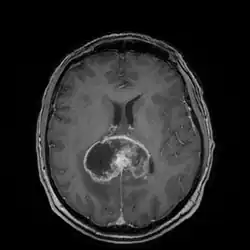

Die Diagnose wird zunächst durch bildgebende Verfahren wie Computertomographie (CT) oder Magnetresonanztomographie (MRT) gestützt. In der CT-Bildgebung mit Kontrastmittel erscheint das Glioblastom unregelmäßig geformt mit randständig starker Kontrastmittelaufnahme (ringförmiges Enhancement). Bei kleineren Tumoren ist dieses ringförmig konfiguriert, bei größeren bildet es eine girlandenartige Formation aus. In der Umgebung des Tumors bildet sich typischerweise ein erhebliches Ödem aus. Der MRT-Befund ist recht typisch: Die soliden Anteile des Glioblastoms reichern Kontrastmittel stark an, dagegen heben sich die Aussparungen durch zystische Anteile und die Blutungen ab. Letztendlich wird die Diagnose am Tumorgewebe, das bei einer stereotaktischen Hirnbiopsie oder Tumorresektion gewonnen wurde, neuropathologisch bestätigt. Im Einzelfall werden Supplementäruntersuchungen wie Elektroenzephalografie und Lumbalpunktion durchgeführt, die der Einschätzung der Anfallsneigung bzw. der differentialdiagnostischen Abgrenzung gegen Hirnabszesse oder Lymphome dienen.

_im_MRI_preoperativ_und_postoperativ.png)

Die neurochirurgische Operation mit Verminderung der Hauptmasse des Tumors (Tumorreduktion) kann das Fortschreiten der Erkrankung verlangsamen, aber nicht dauerhaft verhindern, da praktisch immer einzelne Tumorzellen das gesunde Gehirngewebe schon infiltrativ durchwandert haben und deswegen eine vollständige Tumorentfernung nicht möglich ist. Der Eingriff kann stereotaktisch oder offen durchgeführt werden.[16][23]

Ob ein chirurgischer Eingriff möglich ist, hängt von der Lokalisation des Tumors und dem Allgemeinzustand des Patienten ab. Eine möglichst vollständige Entfernung ist mit längerem Überleben assoziiert.[16][23]